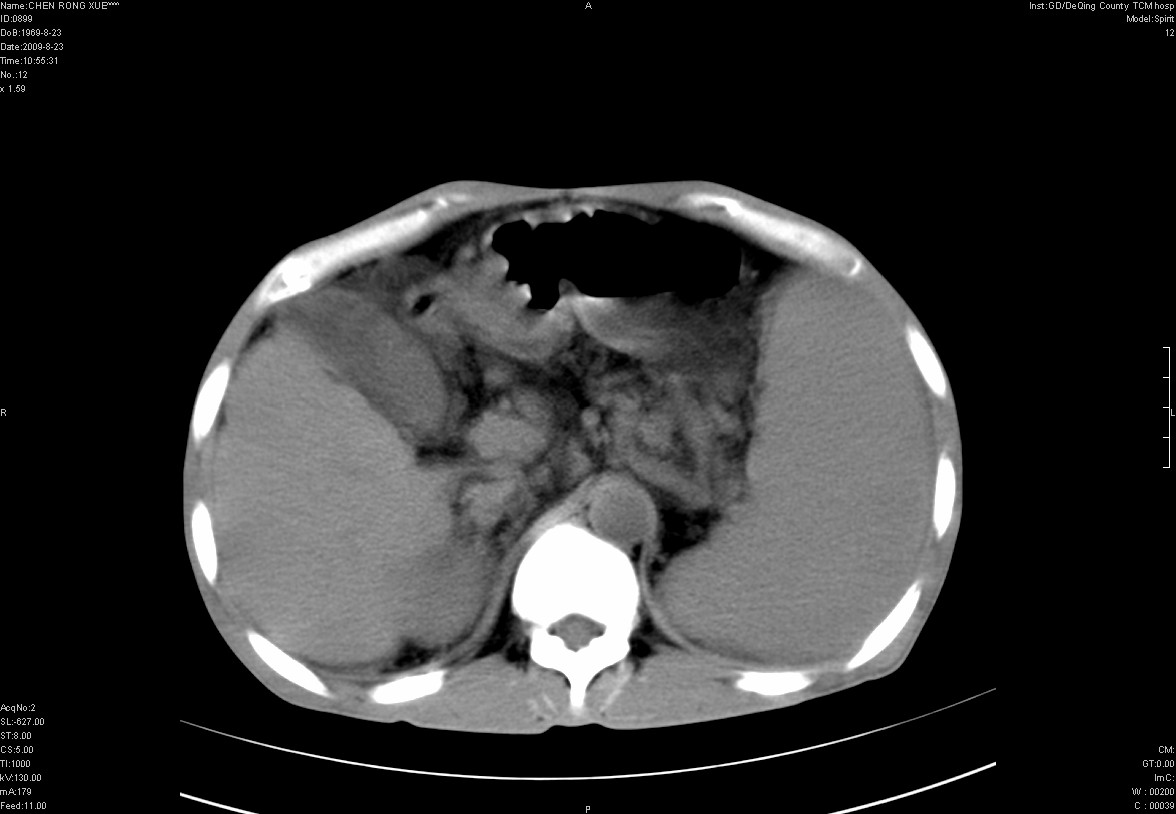

以下是引用zxl51642在2009-8-23 12:56:00的发言:[br]1、肝硬化、脾大;2、慢性胆囊炎;3、右肾占位并右侧腰大肌受侵,考虑恶性可能性大,建议增强扫描进一步检查。

以下是引用qiuleiyu在2009-8-23 15:17:00的发言:[br]1、慢性肝病,肝硬化,脾大,门脉高压。胆囊小结石。[br]2、右肾明显肿大,伴片状低密度灶,累及右侧腰大肌,肿瘤及炎症性病变皆有可能大,建议增强。

以下是引用zjzjr在2009-8-23 17:42:00的发言:[br]1、慢性肝病,肝硬化,脾大,门脉高压。胆囊小结石。[br]右肾脓肿波及肾周,建议增强